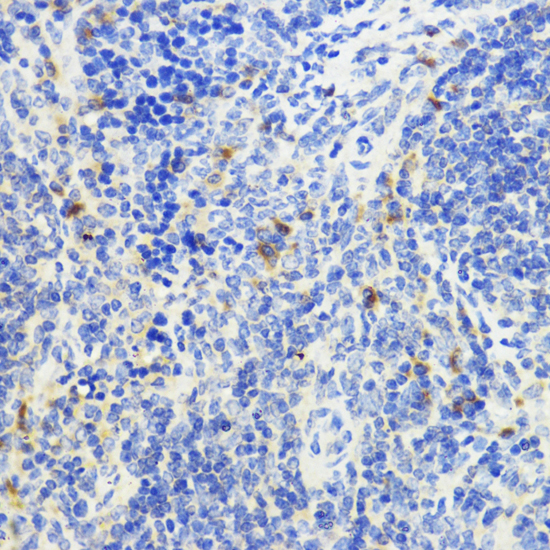

Immunohistochemistry of paraffin-embedded mouse spleen using IL10 antibody at dilution of 1:200 (40x lens).